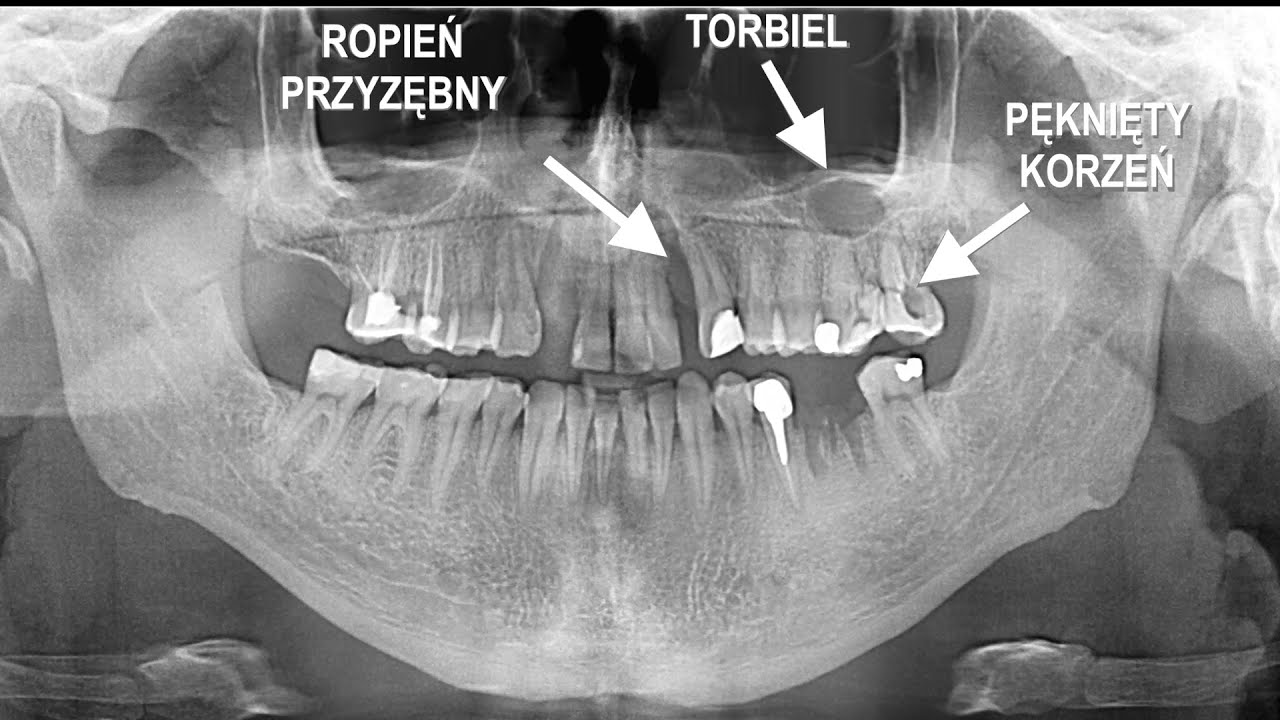

Die Röntgenuntersuchung ist eine grundlegende Zusatzuntersuchung in der Zahnheilkunde, die es ermöglicht, eine korrekte Diagnose zu stellen und eine angemessene Behandlungsplanung vorzunehmen.

Digitale Radiovisiographie ist eine Reihe von Geräten, mit denen Sie ein Röntgenbild auf einfache und sichere Weise für den Patienten innerhalb weniger Sekunden auf dem LCD-Bildschirm erhalten können. Mit einer speziellen Software können wir die Länge der Wurzelkanäle messen und die Knochendichte überprüfen. Die für die Bilder benötigte Röntgendosis wurde im Vergleich zu Filmbildern um das Zehnfache reduziert.

Die 3D-Computertomographie, ist eine neue Qualität in der zahnmedizinischen Diagnostik. Das 3D-Bild ermöglicht eine detaillierte Analyse der anatomischen Strukturen und deren dreidimensionale Rekonstruktion. Dies garantiert sowohl eine korrekte Diagnose und Behandlungsplanung als auch die laufende Kontrolle und Auswertung der Ergebnisse. So können wir den Bereich, „in dem sich die Schmerzquelle befindet“, genau identifizieren. Computertomographische Untersuchungen sind ein unschätzbares Hilfsmittel in der zahnmedizinischen Diagnostik, insbesondere in den Bereichen: Implantologie, Endodontie, Kieferorthopädie, Chirurgie.